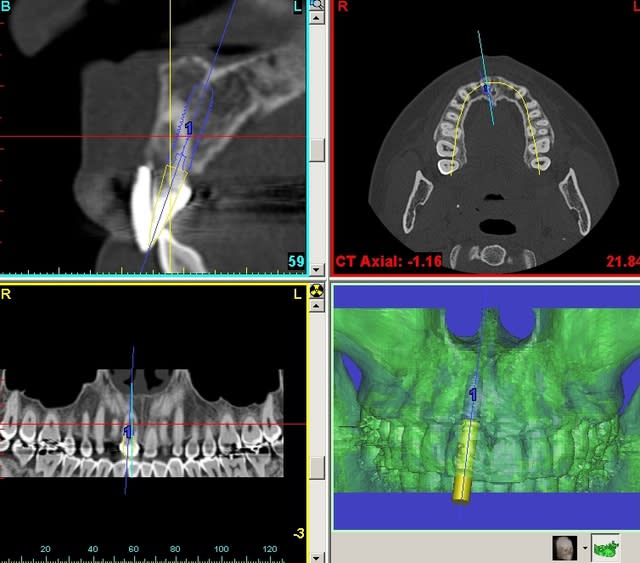

pluton

18/10/2011 à 12h22

joli D57...;-)

çà manque un peu de cas en ce moment...alors en voilà un ptit au passage...

11 avec résorption interne

EII avec MCI sur du dentium (4.5/14) comblement du gap vestibulaire avec du kasios tcp (très constant dans les résultats...et très économique)

pas de photos de chir par contre...j'ai du les effacer par erreur...grrrr...

la prothèse d'usage a été réalisée par ma petite associée...mais j'étais là pour superviser et faire quelques photos...;-)

Planif eampkx - Eugenol